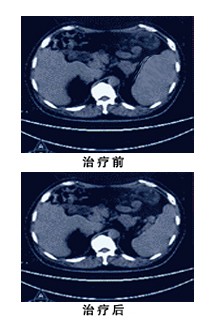

患者刘泉(化名),男,65岁,广州人。患者于2013年5月发现结肠息肉恶变并浸润至膀胱,于2013年6月22日做结肠癌根治术并把部分膀胱切除。病理检查显示:病人的所患的是结肠中分化腺癌侵及肌层和膀胱,癌细胞已经转移到局部的淋巴结。

病人手术后经4个疗程的化疗后,采用WB-1无创全身热疗系统进一步治疗预防肿瘤复发。经2个疗程的WB-1无创全身热疗系统治疗,病人已经基本康复并能正常上班。最近PET-CT检查结果显示:病人体内没有残存肿瘤。病人的肿瘤标志物也在正常范围。